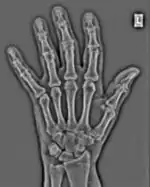

FFTs can also be calculated in two-dimensions to give results such as those in Figure 1.27. Since Fourier analysis generates results in terms of both positive and negative spatial frequencies, these can be plotted in the form of a 2D image so that the maximum frequency lies at the origin and those for the horizontal and vertical directions are shown increasing towards that origin. The modulation at different spatial frequencies is represented using a grey-scale. Low frequency bands can be seen along the horizontal axis in the figure, for example, representing the horizontal periodicity of image data from the fingers, while finer bands along the y-dimension are indicative of a periodicity of image data from the various metacarpophalangeal joints. Higher frequency features can also be seen running diagonally in this 2D-FFT, representative of the trabecular structure of the bones, for example.